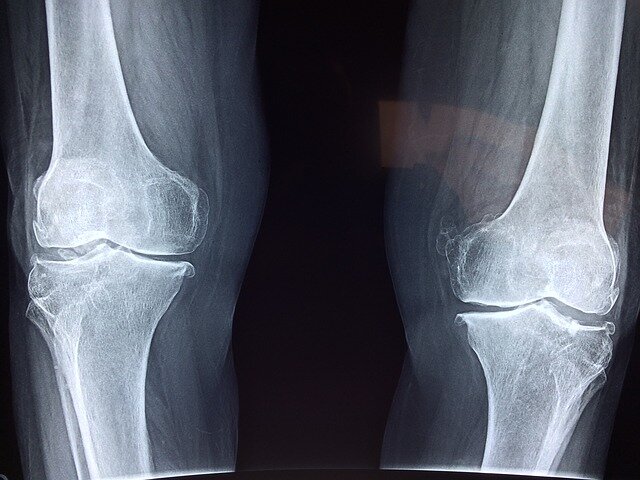

Основные проявления заболевания – деформация сустава, затруднение движения, боль в суставе. Сустав увеличивается в размере. Для постановки точного диагноза необходимо сделать рентгенограмму, чтобы установить степень разрушения сустава. Самая легкая степень – первая. При последней, четвертой стадии, строение сустава полностью нарушено.

Заболевание поражает пожилых людей. С возрастом суставы изнашиваются, хрящи становятся менее прочными. Однако уже в 30- летнем возрасте могут появиться первые признаки разрушения хряща, которые видны лишь на рентгенограмме. Наиболее уязвимая категория – люди, страдающие избыточным весом, нарушениями эндокринной системы, часто подвергающиеся стрессу.